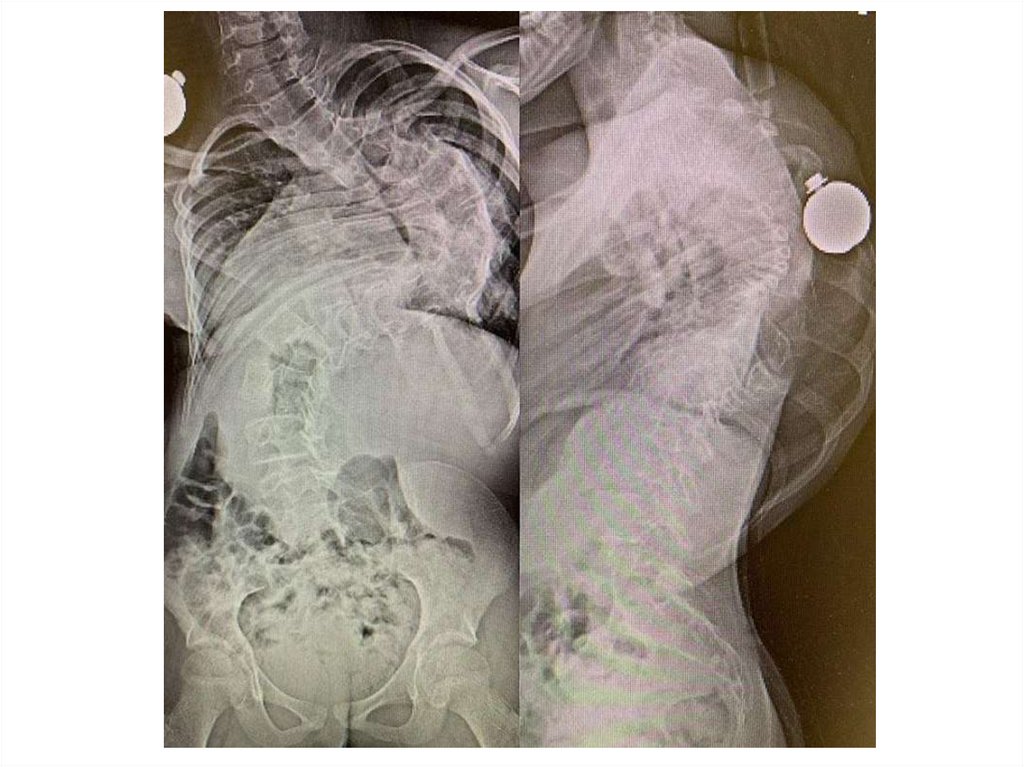

На рентгенограммах грудного и поясничного отделов позвоночника в

двух проекциях лёжа отклонение оси позвоночника влево на уровне Th4Th12, угол сколиоза 650 (4 степень сколиоза) с правосторонней

противодугой на уровне Th12-L4, угол сколиоза 450. Признаки

патологической ротации тел позвонков 4 степени. Грудной кифоз усилен

(угол кифоза 720). Вентральная клиновидность тел грудных позвонков на

высоте кифоза. Снижение высоты межпозвонковых дисков.